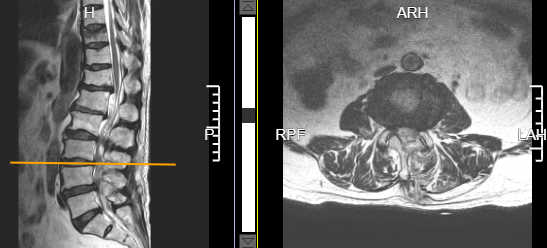

术前腰3/4椎间盘突出并椎管狭窄